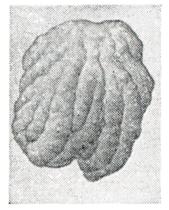

Аденоиды — опухолеподобная масса бледно-розового цвета, располагающаяся на широком основании в области свода глотки. Своей неровной поверхностью они иногда напоминают петушиный гребень (рис. 3). Кроме основной массы аденоидов, большое значение имеют боковые образования, возникающие в результате гипертрофии фолликулярного аппарата слизистой оболочки глотки; они нередко заполняют глоточные карманы и устья слуховых труб. У детей в начале развития аденоидов бывают обычно мягкой, тестовато-рыхлой консистенции. С возрастом и в результате повторных воспалений начинается атрофия лимфоидной ткани и соответственно наступает разрастание соединительной ткани. Аденоиды при этом постепенно становятся более плотными и уменьшаются в объеме. Одновременно меняется их цвет — от красного до бледно-розового или серо-розового. При гистологическом исследовании удаленных аденоидов в лимфоидной ткани чаще обнаруживаются признаки воспаления. Независимо от выраженности гиперплазии лимфаденоидной ткани в 75—80% случаев и более определяются различные формы хронического аденоидита. Клиническая картина. Симптомы аденоидов весьма разнообразны. Основные из них — периодическое или постоянное закладывание носа с обильными выделениями, заполняющими носовые ходы, что нарушает кровообращение в полости носа и носоглотки. Возникают застойные явления в носу и даже в его придаточных пазухах, ведущие к хроническому набуханию и воспалению слизистой оболочки носа, особенно задних концов носовых раковин, и к обильному скоплению густой вязкой слизи. Часто развивается хронический насморк. В результате затрудненного носового дыхания дети с аденоидами спят с открытым ртом, сон их обычно бывает беспокойным, нередко сопровождается громким храпением и даже приступами удушья вследствие западения корня языка при отвисшей нижней челюсти; утром дети встают вялыми и апатичными, нередко с головной болью.

Рис. 3. | ||